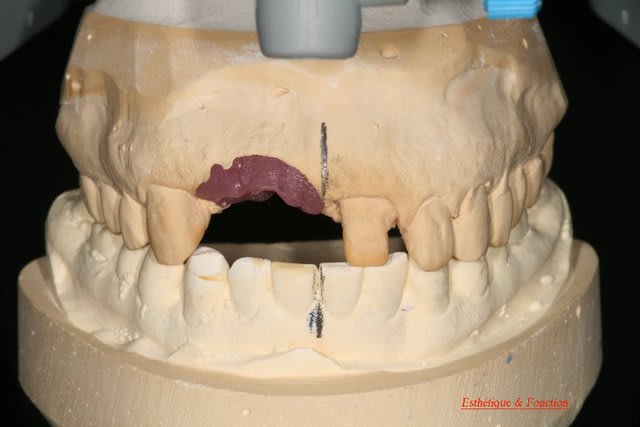

tu devrais faire faire par ton prothésiste un wax avec les dents en blanc et les tissus mous qu'il te manque en rouge afin de bien visualiser tous les tissus qu'il te manque.

Bon voila le scann de 11-12 (pas 21-22 comme noté)

C'est vrai que j'ai à mort d'os en épaisseur.

Le manque est surtout en hauteur.

Dans tous les cas je refais 21 en même temps.

Bon ben j'ai implanté avant d'avoir refait la 21. Du coup j'ai mésialé la pose de 11 pour compenser la distalisation de 21.

Au final je n'ai pas fait de greffe osseuse... et j'ai réalisé une technique de rouleau sur 11-12 mais je reste un peu court à mon goût.

J'ai mis en place des transitoires sur 11-12-21 pour temporiser 3 mois pour voir la maturation des tissus mous.

Je mets quelques photos de la patiente au cab et du prothèsiste d'Epinal.

La vraie difficulté a été de retrouver le milieu incisif pour déterminer la position des implants.